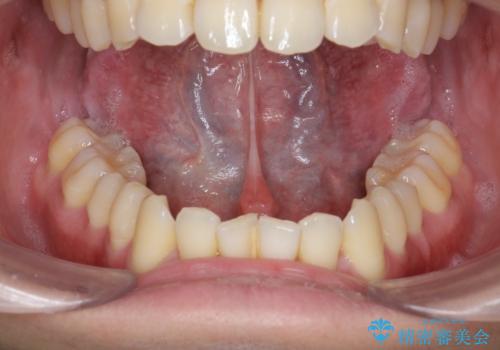

- 舌の動きが舌小帯により制限され、滑舌の改善を求めて来院されました。

形成手術を行うことで、舌の動きをより自由に行うことが期待できます。